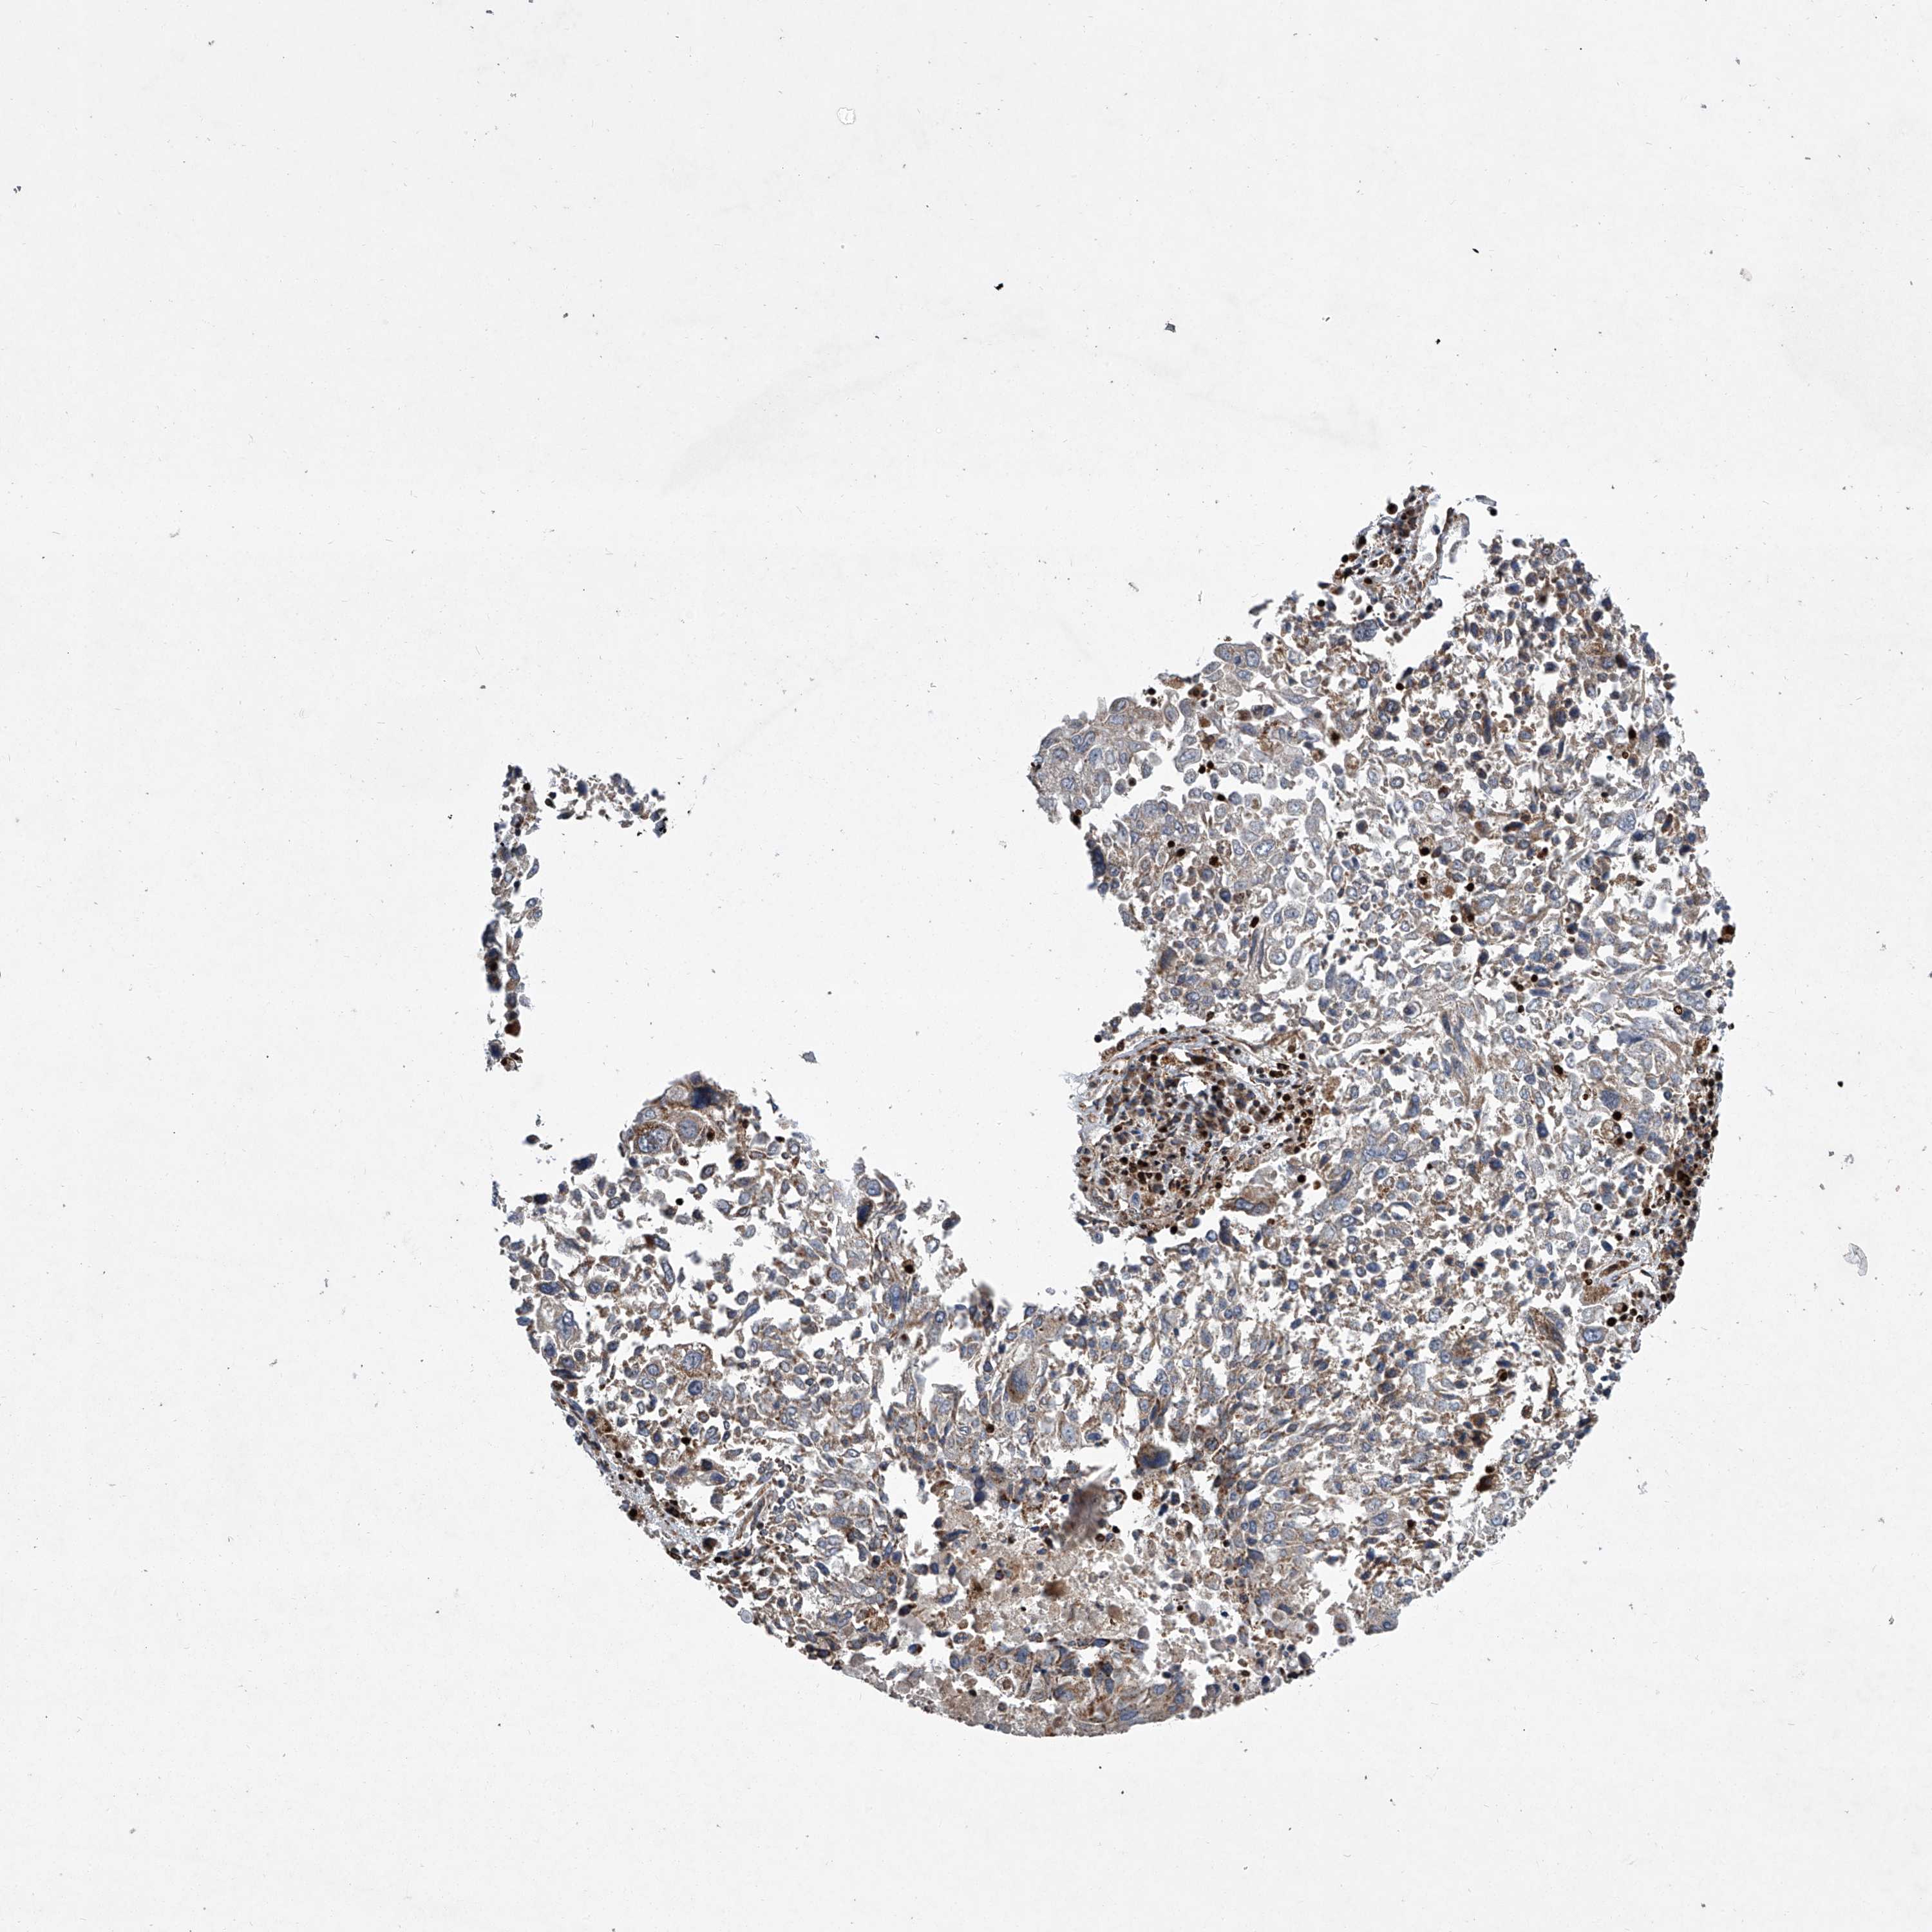

CANCER LUNG CANCER Show tissue menu

LUAD TCGA LUAD VALIDATION LUSC TCGA LUSC VALIDATION PROTEIN LUAD CPTAC PROTEIN LUSC CPTAC PROTEIN EXPRESSION

ANTIBODIES

AND

VALIDATION